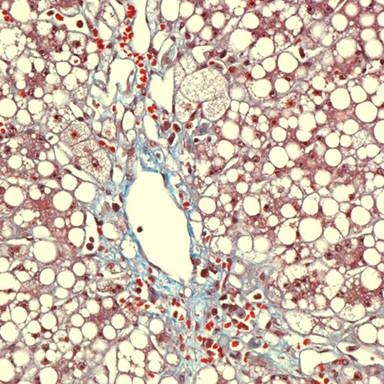

Analysis of serum amino acids revealed elevated levels of glutamine, alanine and proline. In addition, lysine, ornithine and arginine were mildly elevated. Citrulline, cystine and rest of the amino acids including carnitine levels were normal. Results of microbiologic testing, including PCR-based testing for herpes simplex, varicella zoster and Epstein-Barr virus in the cerebrospinal fluid, and India ink preparation for Cryptococcus and other fungi were negative. The liver biopsy showed prominent diffuse macrovesicular steatosis with moderate signs of cholestasis (Figures 2 and 3).

Figure 3. Liver biopsy showing signs of cholestasis with pericentral and pericellular fibrosis. |

Hyperammonemia is well established cause of encephalopathy and coma. In our patient, hyperammonemia progressed to coma with no previous history of liver disease. Hyperammonemia can be primarily seen with hereditary defects in urea cycle enzyme function or can be seen secondary to acute or chronic liver disease, organic acidemias, carnitine deficiency, Reye’s syndrome, infections with urea-splitting organisms, such as Proteus mirabilis and iatrogenic causes including transjugular intrahepatic portosystemic shunting, total parenteral nutrition, and adverse drug effects from valproate, carbamazepine or asparaginase [9, 10, 11, 12, 13, 14, 15, 16]. It has also been described following bone marrow transplantation, lung transplantation or after chemotherapy for leukemia [5, 6, 7, 8]. In the present case, there was no evidence of underlying liver disease or acute hepatitis. Although fluid cultures were positive for Escherichia coli, blood cultures were negative and patient continued to worsen in spite of treatment of infection. The patient was not on any drugs that have been implicated in hyperammonemia. Although the patient had elevations of certain serum amino acids, elevations were inconsistent with any specific urea cycle defect and gene sequencing following recovery of the patient did not reveal any urea cycle defect. The presence of normal urine organic levels eliminated the possibility of methylmalonic, propionic, or isovaleric acidemia as well as primary carnitine deficiency and other defects in fatty acid oxidation as etiologic factors for this hyperammonemia. However, the patient had severe malnutrition and had co-existing intra-abdominal infection at the time of her presentation with hyperammonemia. Also the liver biopsy showed prominent diffuse macrovesicular steatosis with moderate signs of cholestasis (Figures 2 and 3). Our patient most probably fits the profile of “idiopathic hyperammonemia” which is defined based on a plasma ammonia level greater than twice the upper limit of normal, with relatively normal other liver function tests, and in the absence of inborn errors of metabolism or other identifiable causes. Although Reye’s syndrome can mimic idiopathic hyperammonemia, it is rare in adults and our patient had no prodromal viral symptoms or history of aspirin ingestion to support the diagnosis. Also the absence of significant elevation of lysine makes Reye’s syndrome less likely [3].